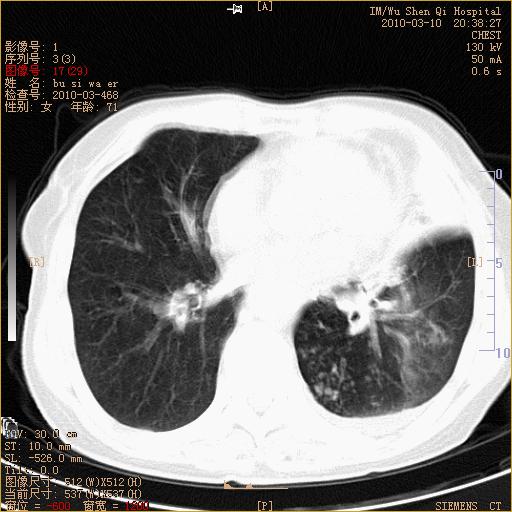

以下是引用随光逐影在2010-3-11 0:41:00的发言:[br]1)考虑左肺及右肺上叶继发性肺结核并左肺炎症感染。2)左侧支气管内膜结核可能;建议必要时行纤支镜检查。3)肺气肿。4)心包膜增厚(或少量心包积液)。5)左侧胸腔积液。